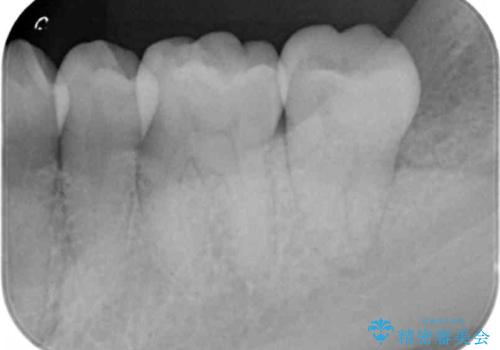

- 奥歯の樹脂の色が気になるとのことで来院されました。

変色しない材料での治療をご希望されたためセラミックインレーでの治療をしていくこととなりました。

継ぎ接ぎになった樹脂の詰め物から一塊のセラミックインレーに置き換えることで着色や二次う蝕のリスクを抑えます。